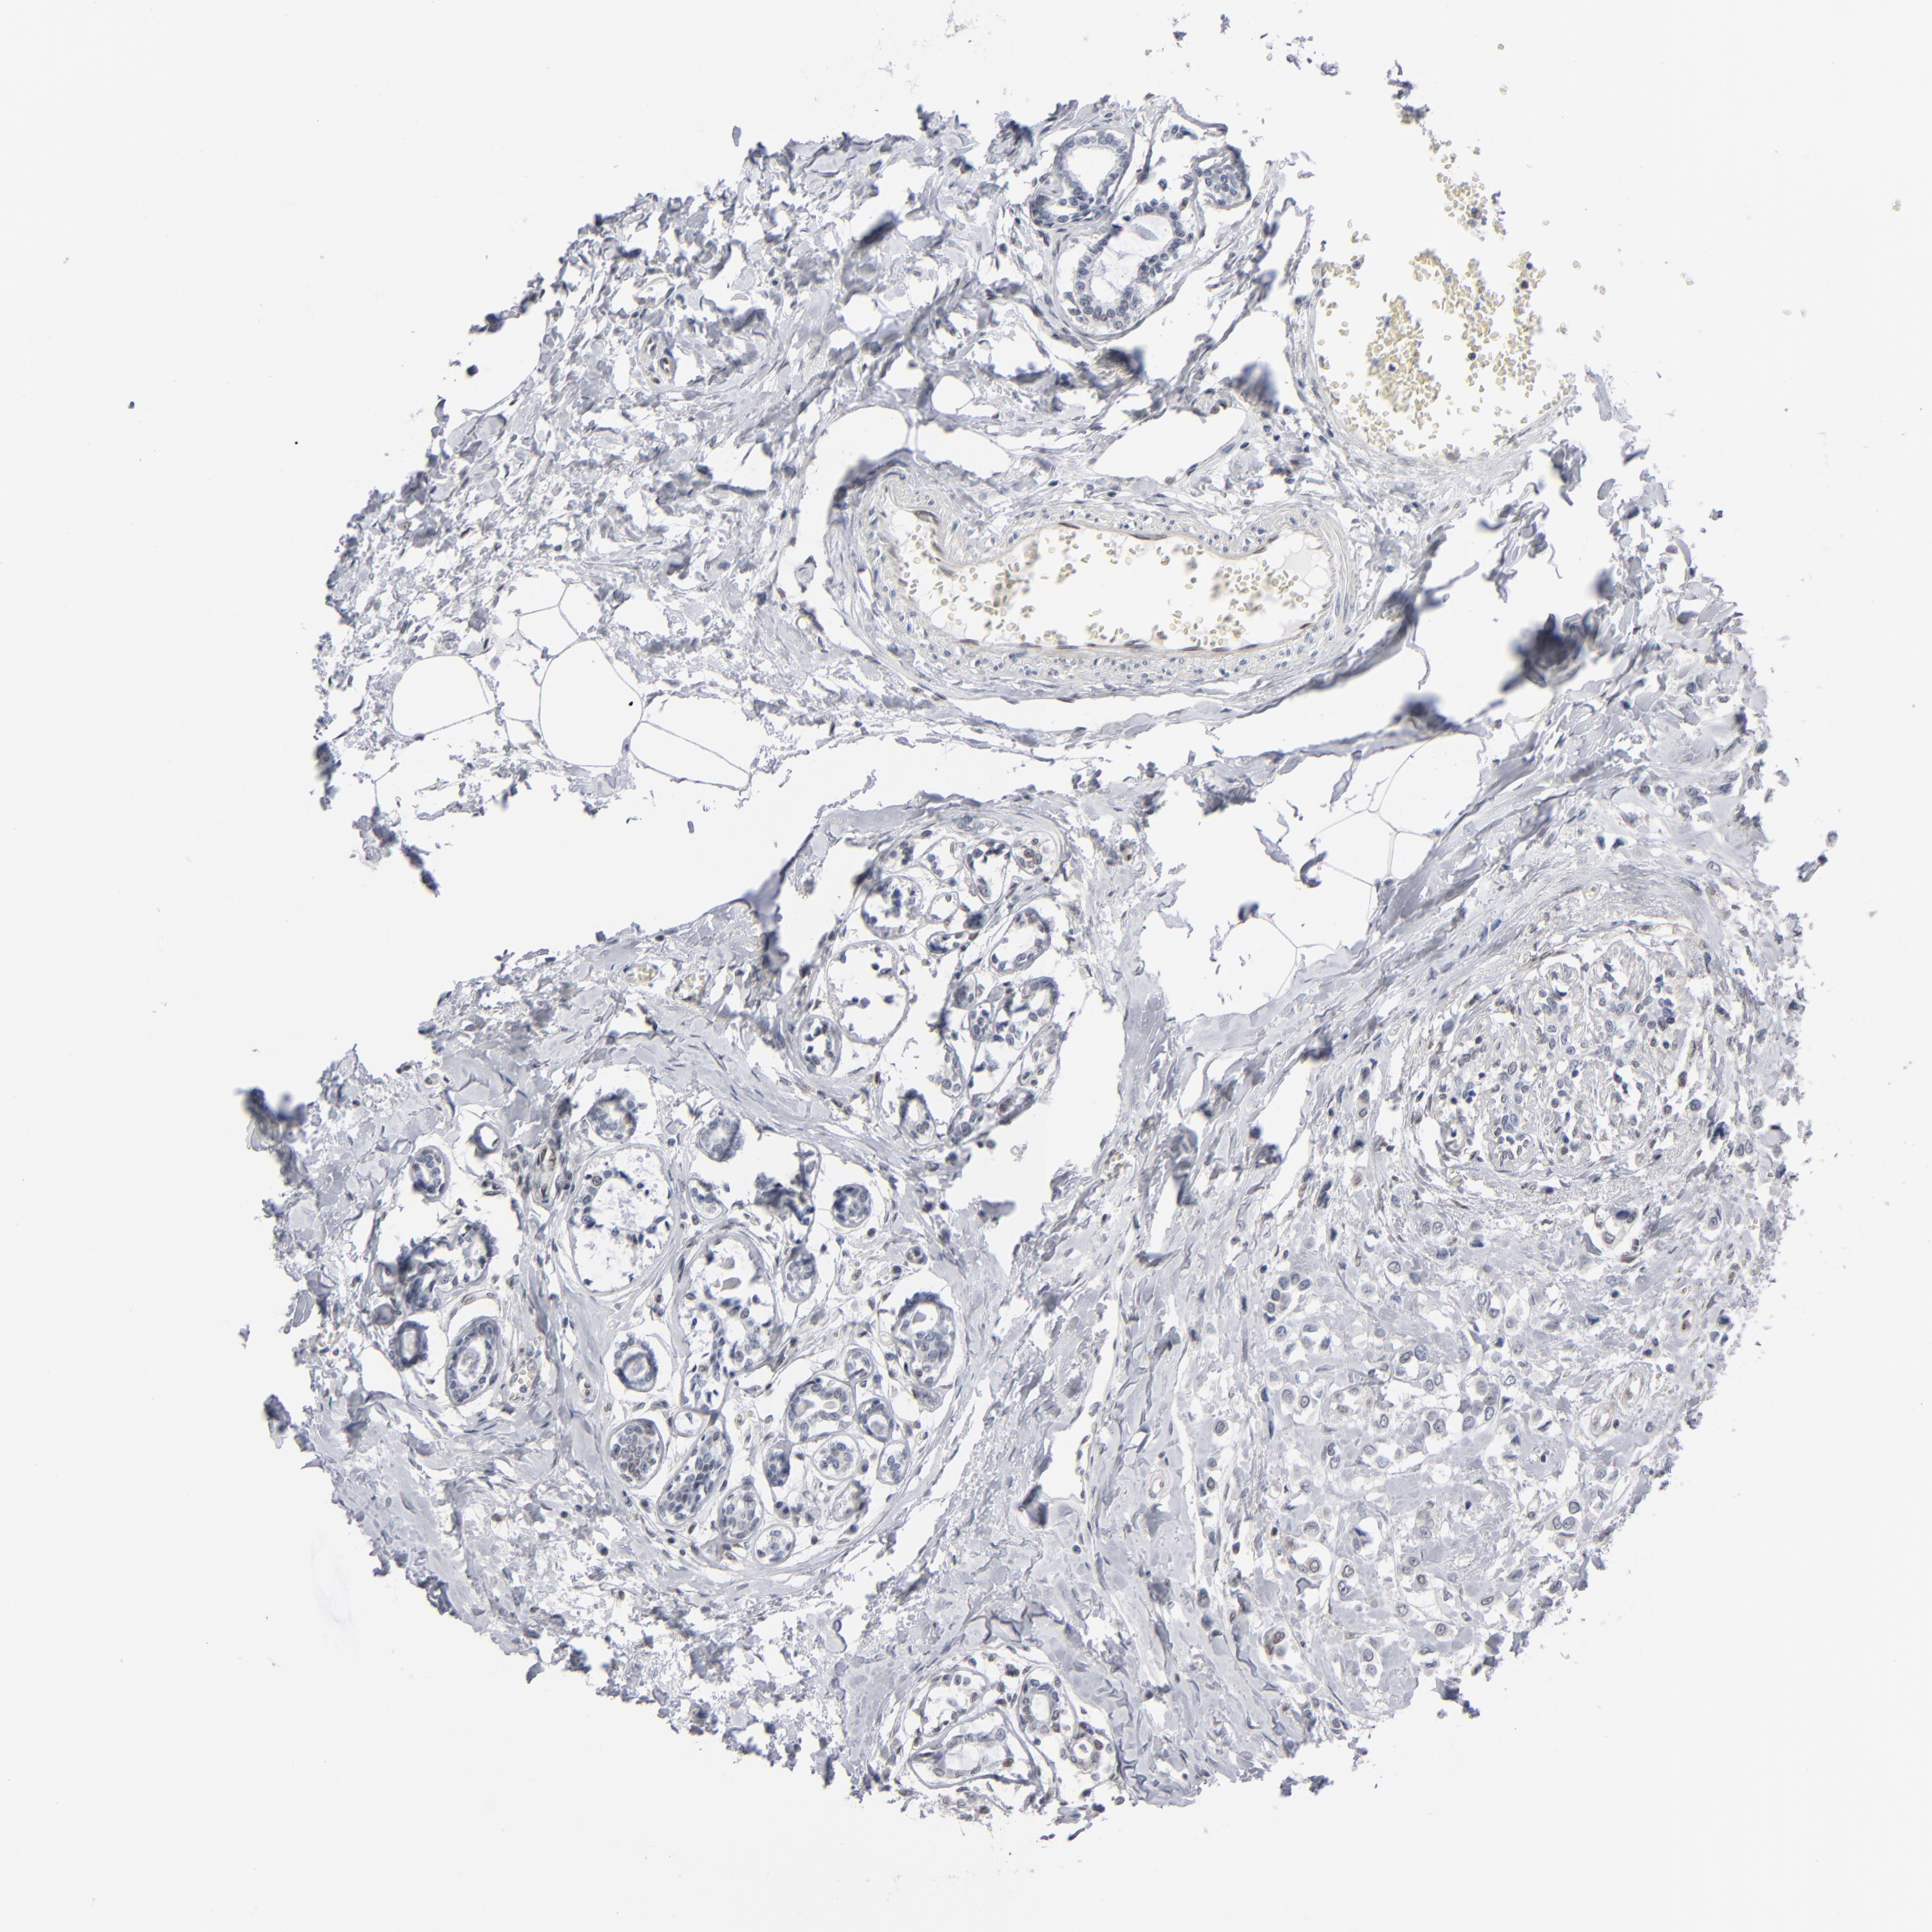

Breast cancer

Human cancer